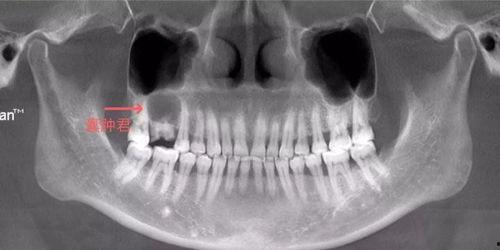

1. 牙根的“真实面目”:原来,烂牙根竟然如此复杂,错综复杂地缠绕在牙槽骨中。

3. 拔牙过程的“惊险”:医生在拔牙过程中,需要克服牙根的顽强抵抗,稍有不慎,就可能伤及周围组织。

2. 术前做好检查:拔牙前,医生会对患者进行详细的检查,确保手术顺利进行。